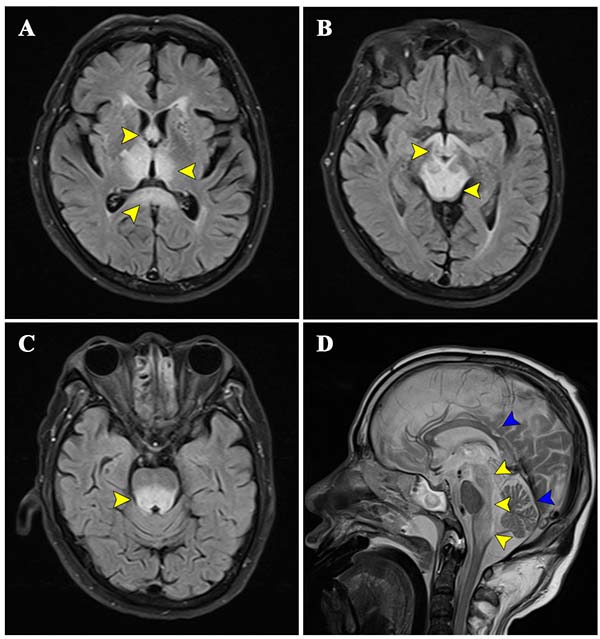

MRI影像显示,WKS表现为一种非典型广泛脑干受累,病变广泛累及中脑、脑桥和延髓的被盖部。典型的WKS主要累及丘脑、乳头体等结构,而包括延髓在内的脑干广泛受累罕见。本例报道患者因昏迷伴顺行性遗忘和间断性意识障碍入院,既往30年酗酒史。入院查体发现眼震。血清维生素B1浓度为21.4 nmol/L(参考值70-180 nmol/L)、血清和脑脊液自身免疫性脑炎抗体(NMDAR, AQP4, LGI1, GAD65, GFAP, AMPA2, GABABR, mGluR5, CASPR2, Hu, Ri, Yo, CV2, Ma2/Ta, Amphiphysin)均为阴性。结合MRI的特征性表现,最终确诊为WKS。虽然医疗团队给予静脉补充维生素B1治疗和全力抢救,但患者昏迷无缓解,并进展为中枢性呼吸衰竭。

维生素B1长期缺乏引起的脑代谢性疾病,临床表现为顺行性遗忘、意识障碍,查体可见眼震和共济失调,脑MRI的特征性表现为乳头体、丘脑、中脑导水管周围及脑桥T2/FLAIR高信号。本病例呈现罕见的广泛脑干病变,累及中脑、脑桥及延髓被盖部(基底未受累),并涉及穹窿柱、胼胝体等,扩展了WKS的影像学特征,为维生素B1缺乏的神经病理研究提供新依据。